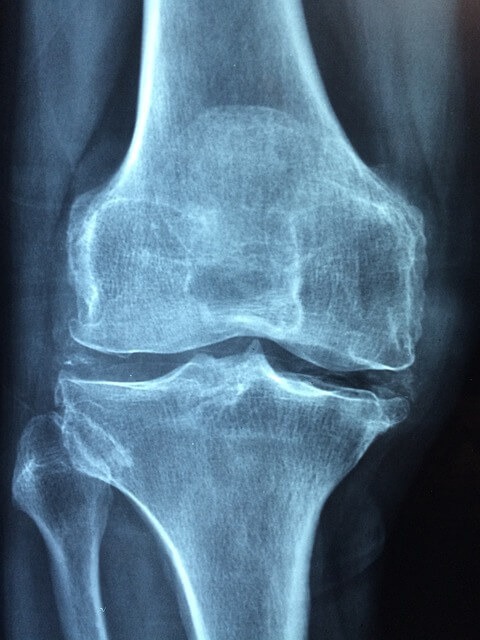

우리의 관절 사이에 있는 연골은 관절의 움직임을 부드럽게 하고, 관절의 하중을 흡수해 준다. 관절의 움직임이 많아지면 연골이 마모되면서 통증이 생기고 관절염이 생기기도 한다.

콘드로이친은 연골의 주요 성분 중 하나로, 관절의 건강을 유지하는 데 중요한 역할을 한다.

콘드로이친은 연골의 주요 구성 요소 중 하나로, 연골 분해를 억제하는 역할을 한다. 이는 관절을 보호하고 손상을 줄여주는 역할을 한다. 연골은 시간이 지남에 따라 자연적으로 마모되거나 손상될 수 있는데 콘드로이친은 이를 예방해 준다.